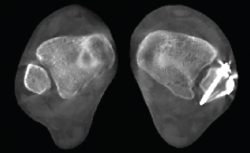

Figura 5. Artropatía de la columna medial en paciente operada de artrodesis astragaloescafoidea.

Figura 6. Artropatía de la columna medial.

- Inestabilidad de la columna medial o inestabilidad tarsometatarsiana. Valoración y estudio de la columna medial en carga (Figuras 5 y 6).